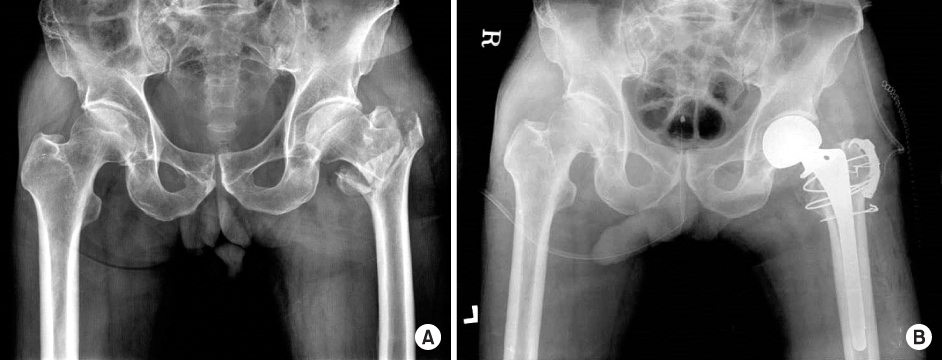

Fig. 3

(A) Preoperative radiograph of a type D greater trochater (GT) fracture in an 85-year-old woman. (B) The displaced GT fragment was reduced and fixed with cerclage wiring and non-absorbable suture. (C) Postoperative radiograph after bipolar hip arthroplasty and fixation of GT fracture with cerclage wiring and non-absorbable suture.

Fig. 3 (A) Preoperative radiograph of a type D greater trochater (GT) fracture in an 85-year-old woman. (B) The displaced GT fragment was reduced and fixed with cerclage wiring and non-absorbable suture. (C) Postoperative radiograph after bipolar hip arthroplasty and fixation of GT fracture with cerclage wiring and non-absorbable suture.